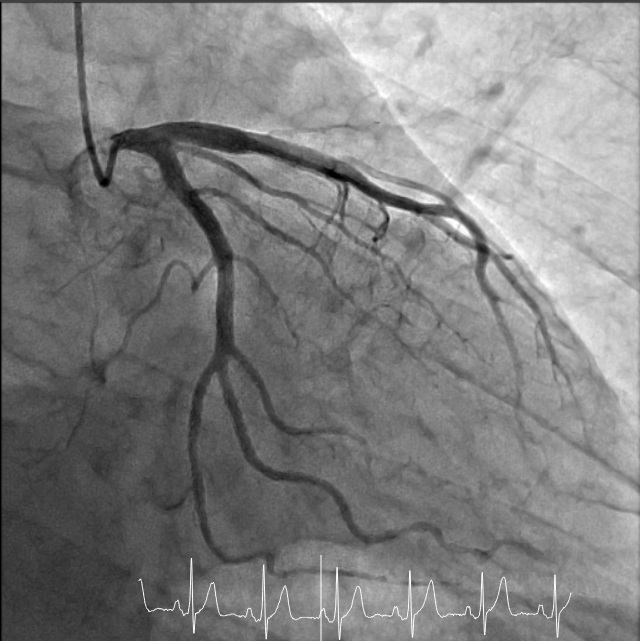

血管はX線写真では写す事が出来ません。しかし造影剤という薬を使用することで、血管を写す事が出来ます。心臓カテーテル検査では直径約1~2.5mm程のカテーテルと呼ばれる細い管を心臓まで到達させ、その管を使って造影剤を注入する事で心血管の血流を撮影します。

心臓カテーテル検査とは、カテーテルを手首またはそけい部の動脈から心臓の血管(冠動脈)や心臓の中まで挿入し、心室内の圧を測定したり造影剤を使用して冠動脈の状態を見たり、心臓の動きを観察する検査です。血管からカテーテルを挿入して行う検査のため、2~3日程度の入院が必要となります。

心臓カテーテル検査の結果、血管のつまり(狭窄)を発見した場合は、カテーテルを使用した治療を行います。血管を広げる方法は主にバルーン治療やステント治療があります。